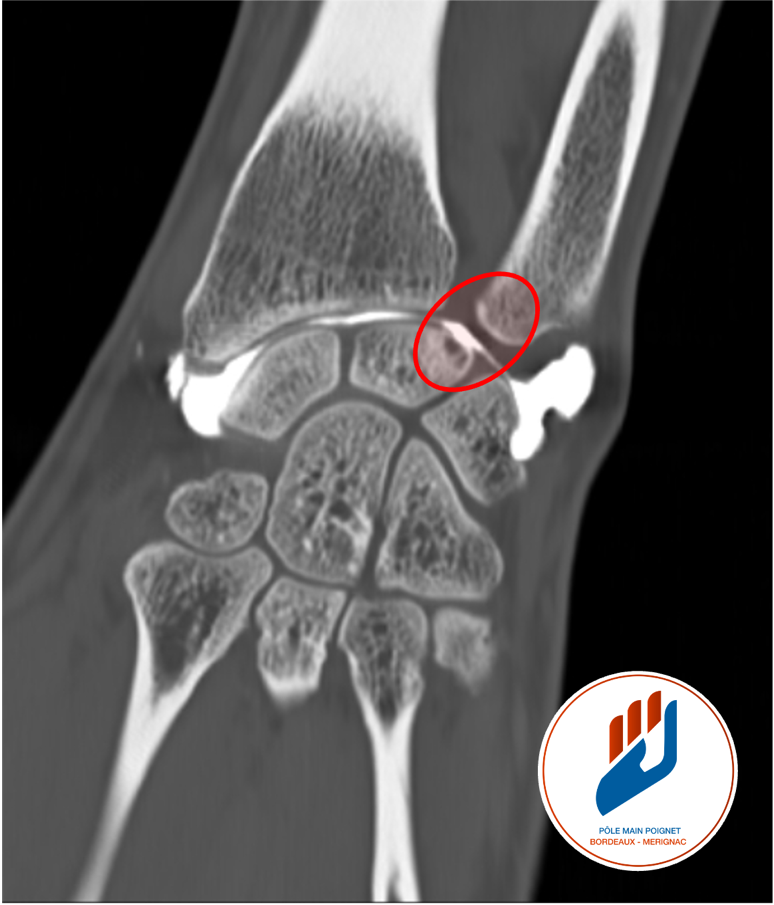

Des examens d’imagerie sont ensuite prescrits pour confirmer le diagnostic. Les radiographies standards du poignet permettent de mesurer la longueur relative du radius et du cubitus (variance ulnaire). Une IRM ou un arthroscanner permet de visualiser les lésions du fibrocartilage triangulaire et l’état des surfaces articulaires (le cercle rouge sur la photo montre une usure du cartilage sur le pôle proximal du semi-lunaire).

Lorsque le cubitus est clairement trop long ou si le poignet présente des lésions cartillagineuse entre l’ulna et le semi-lunaire, une ostéotomie de l’ulna est indiquée. Cette opération consiste à retirer quelques millimètres d’os au niveau du cubitus (zone entouré par le cercle rouge sur la photo) et à fixer l’os avec une plaque et des vis. Ce geste corrige durablement le conflit mécanique et permet une amélioration significative des douleurs. L’immobilisation post-opératoire est de 6 à 12 semaines, et la rééducation se poursuit sur plusieurs semaines. La plupart des patients reprennent une activité professionnelle manuelle entre trois et six mois après l’intervention.